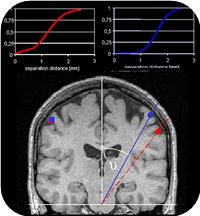

- Zusammenhang Veränderung der Wahrnehmung <–> Reorganisation